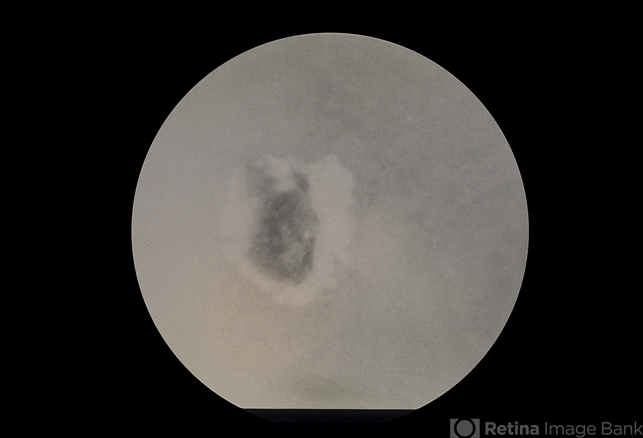

- ARMD SRNVM

- Condition/keywords

- subretinal neovascularization (SRNV)

- ARMD, SRNVM, 79-year-old white female, 20/300.